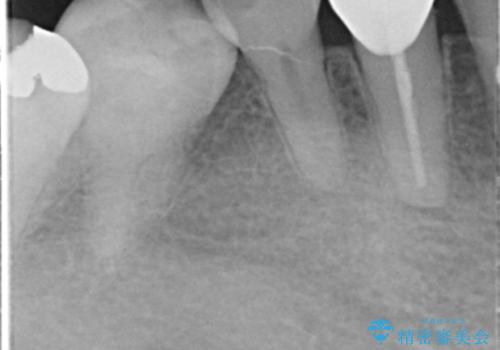

- 子供のころに4本抜歯してワイヤー矯正をしたとのことでした。

最近右下の犬歯の根の先付近の歯茎に何かできており、違和感があるとのでした。

CTでみたところ、下の犬歯が内側に倒れこんでおり、根の先が顎の骨から出かかっている状態でした。おそらくその影響で犬歯の神経が失活してしまったのであろうと思われます。(フェネストレーションといいます)

検査した結果下の両側の犬歯の神経が失活しており、根の治療が必要な状態でした。